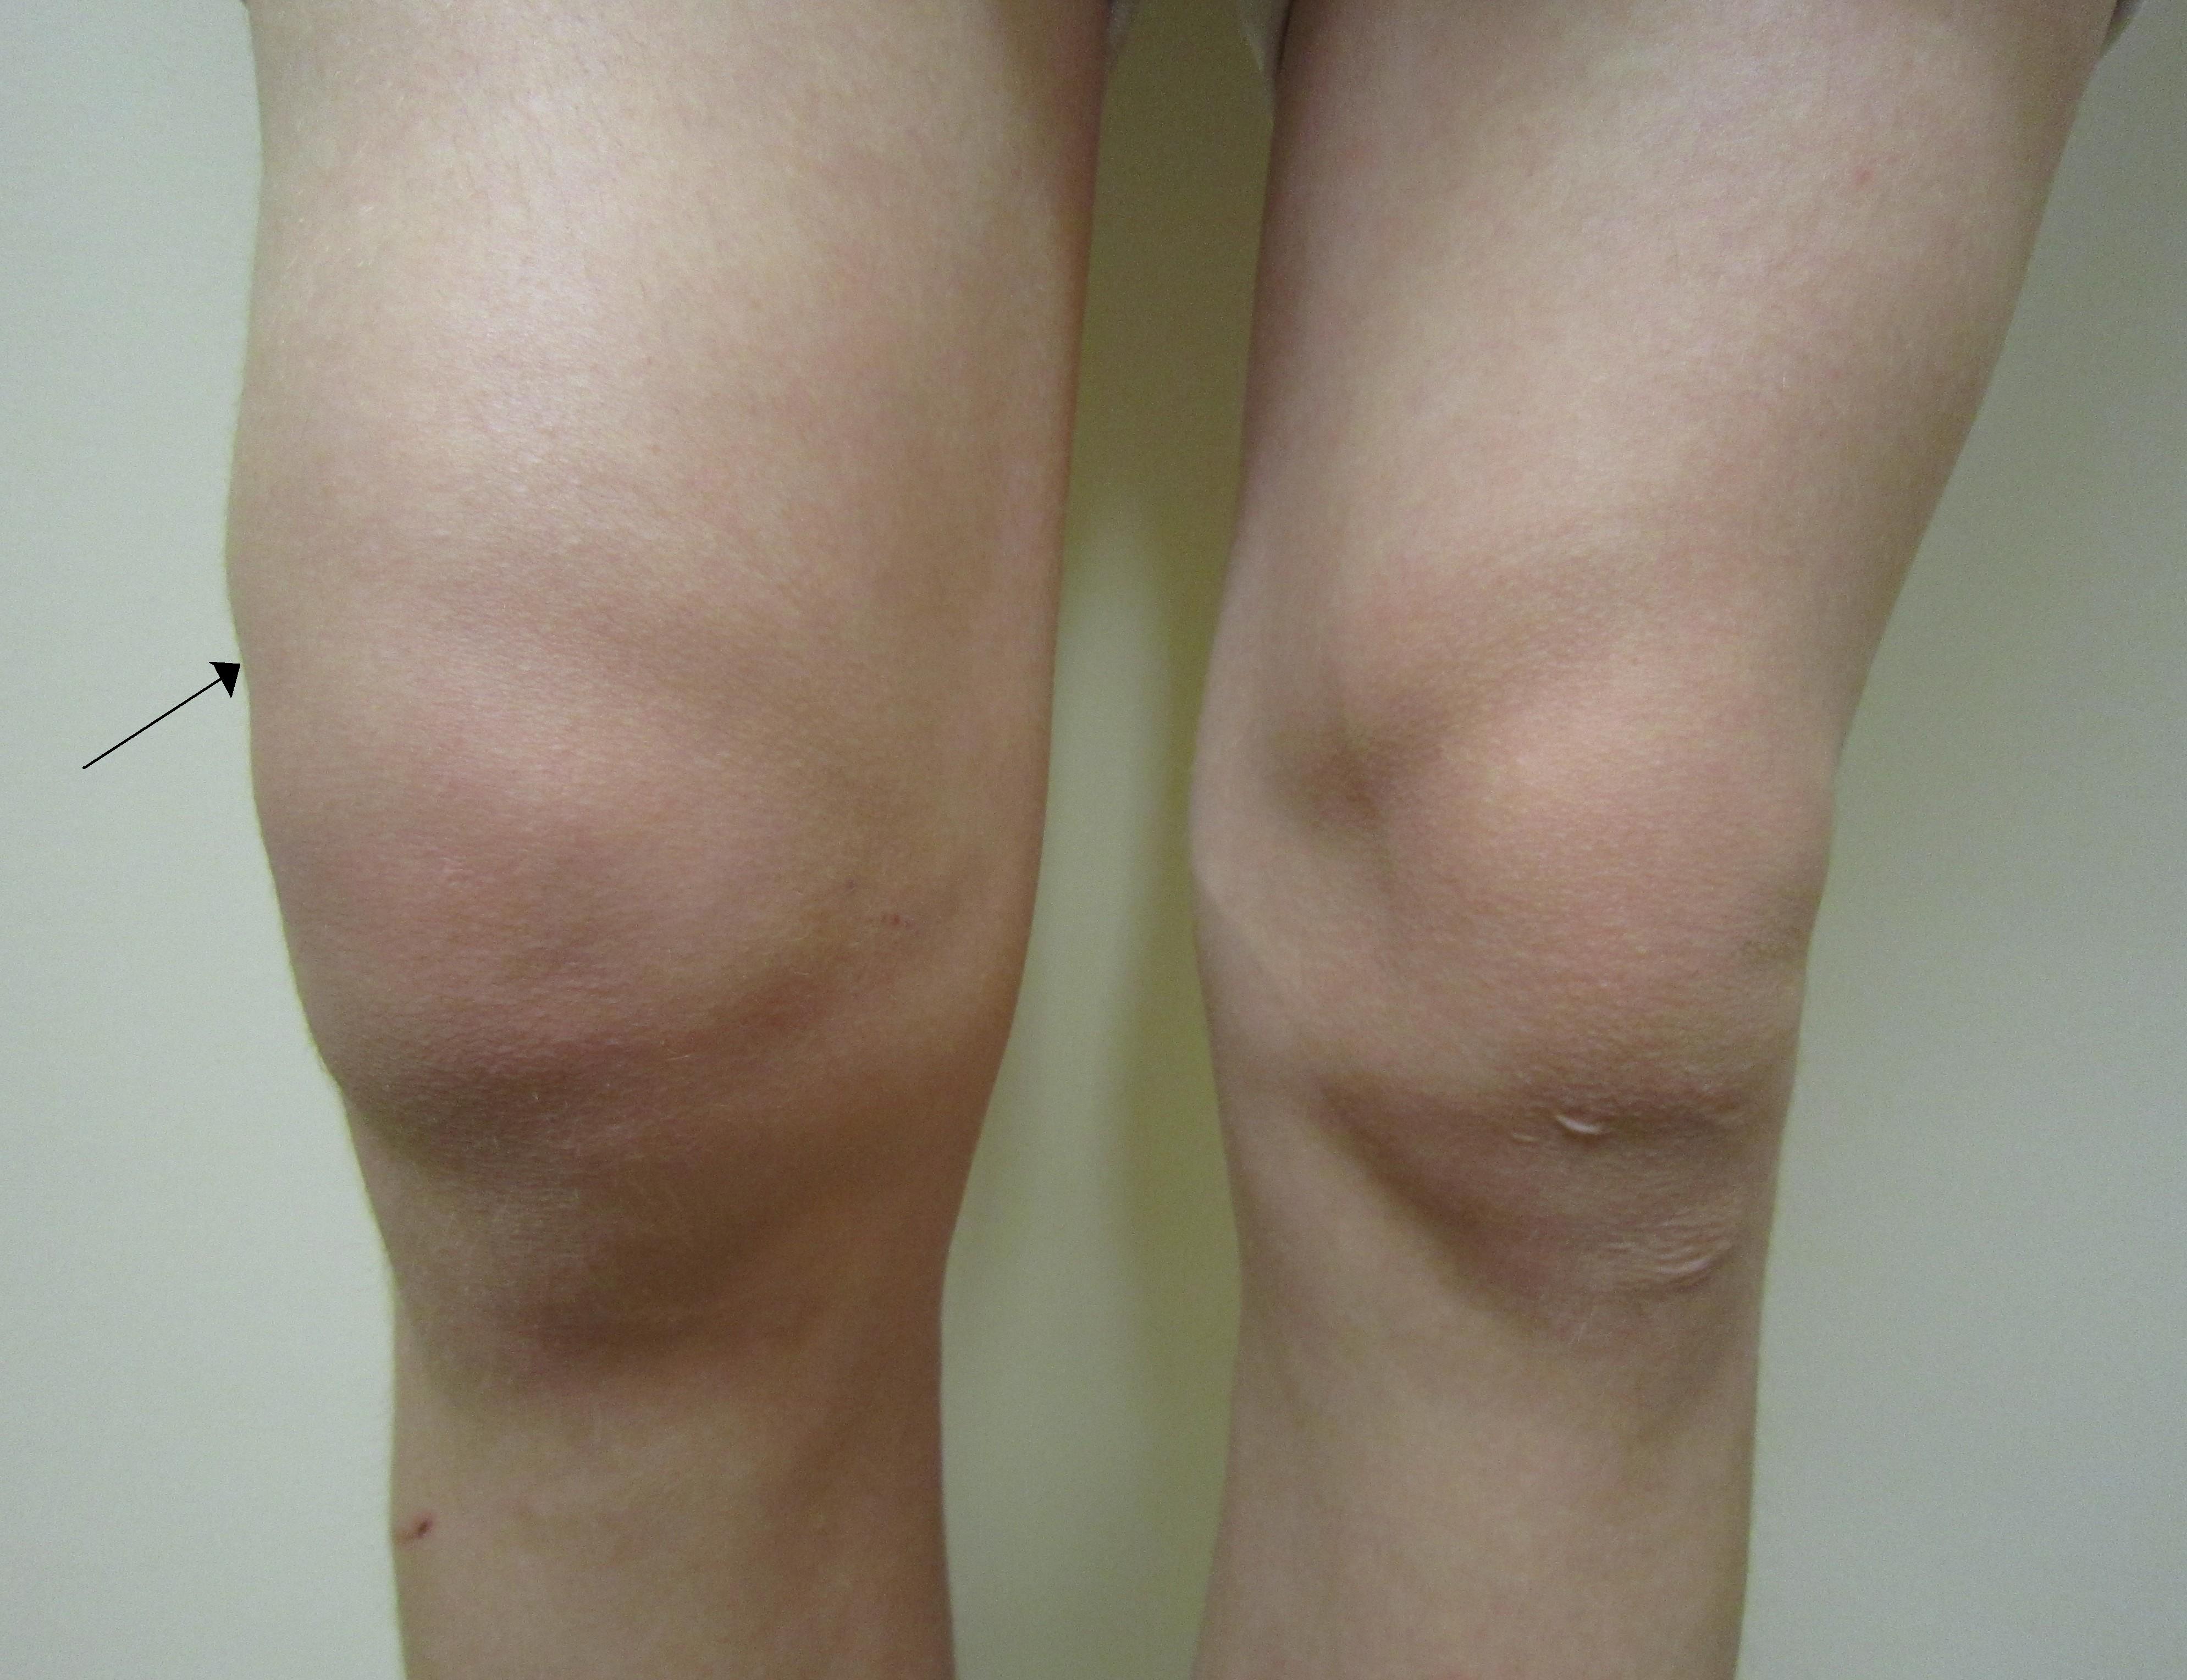

Torbiel Bakera to wypełniona płynem narośl zlokalizowana za kolanem. Powoduje wybrzuszenie i uczucie...

Zasadniczo ból kolana może mieć różne przyczyny. Ostre objawy są często wywoływane przez uraz stawu ...